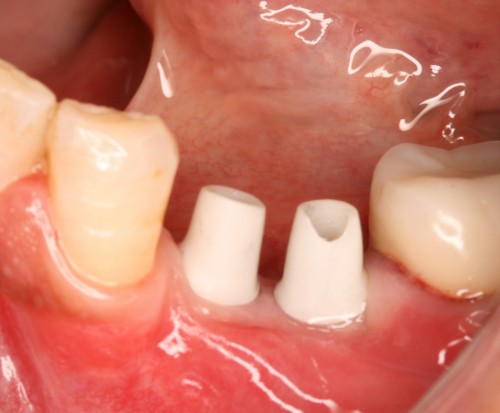

術前

インプラント挿入

土台装着

被せ物装着

同パノラマ写真

被せ物装着後歯肉の盛り上がり